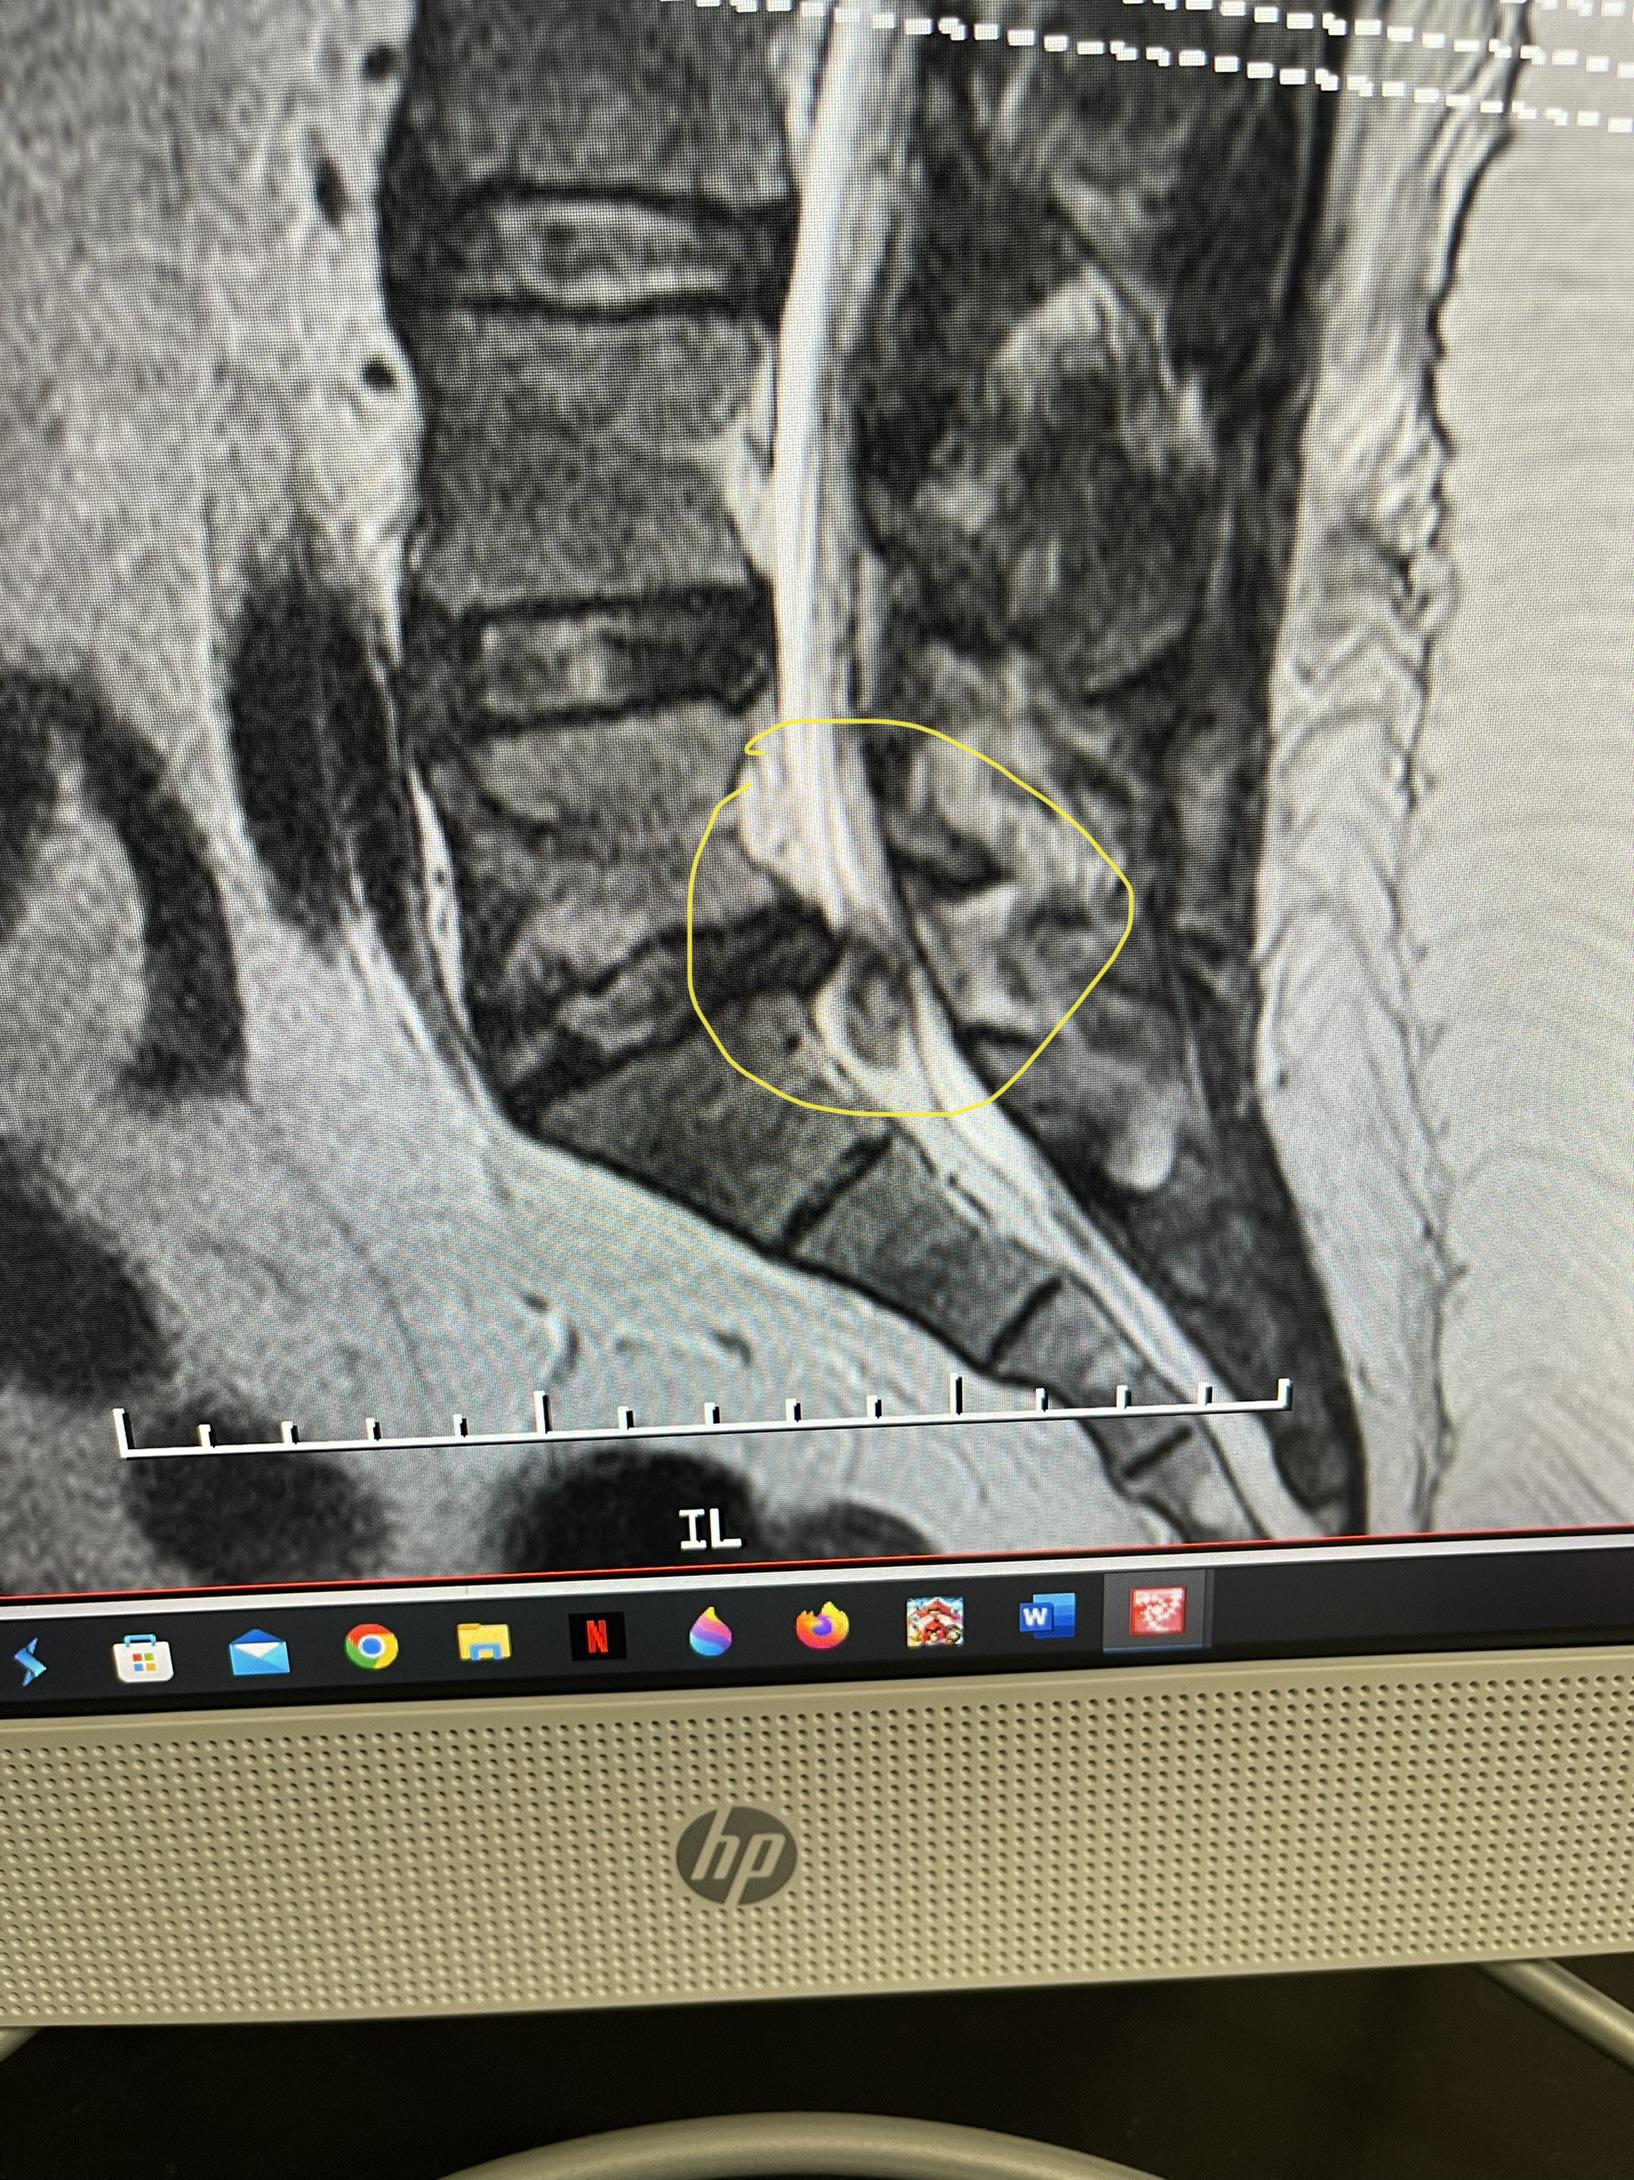

Herniated Disc Pain Down Leg . A herniated disc in the lower back can cause a range of symptoms varying from moderate pain in the lower back and buttock to widespread pain, numbness, and weakness in the leg and foot. While minor cases may be asymptomatic or cause mild. If your herniated disk is in your lower back, you'll typically feel pain in your lower back, buttocks, thigh and calf. If you have a herniated disk in your lumbar spine, the pain might come down your leg, down your butt, over the hip and down the leg, says dr. A herniated disc (also called bulging or slipped disc) occurs when the outer shell ruptures and the nucleus leaks out. Though some people with a herniated disk feel no discomfort, others who have this condition may find that hard to believe. For them, the sharp, intense pain that radiates down. Sciatica most often happens when a herniated disk or an overgrowth of bone puts pressure on the lumbar spine nerve roots.

If you have a herniated disk in your lumbar spine, the pain might come down your leg, down your butt, over the hip and down the leg, says dr. Sciatica most often happens when a herniated disk or an overgrowth of bone puts pressure on the lumbar spine nerve roots. A herniated disc in the lower back can cause a range of symptoms varying from moderate pain in the lower back and buttock to widespread pain, numbness, and weakness in the leg and foot. For them, the sharp, intense pain that radiates down. Though some people with a herniated disk feel no discomfort, others who have this condition may find that hard to believe. While minor cases may be asymptomatic or cause mild. A herniated disc (also called bulging or slipped disc) occurs when the outer shell ruptures and the nucleus leaks out. If your herniated disk is in your lower back, you'll typically feel pain in your lower back, buttocks, thigh and calf.